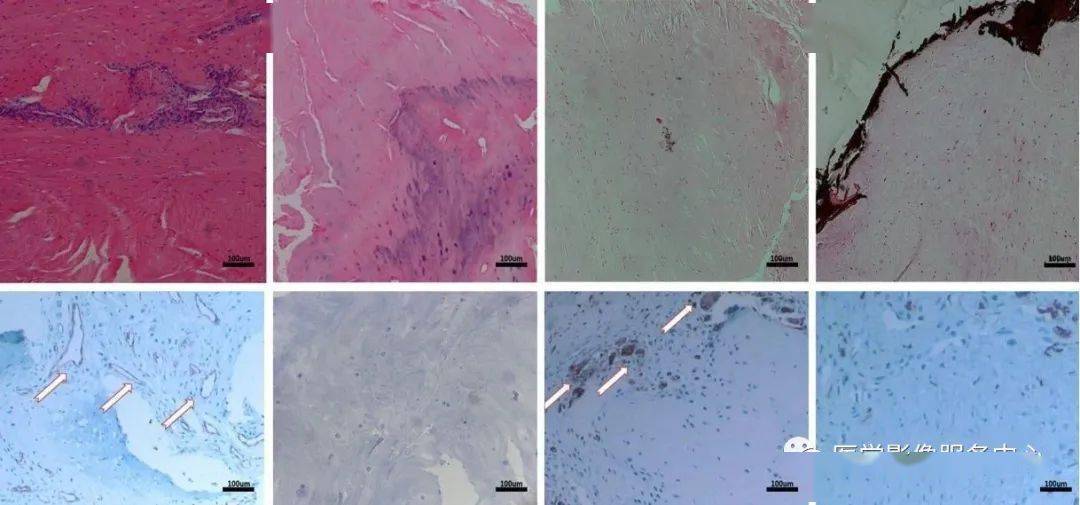

组织学检查提示单HIZ为可见大量新生毛细血管和集的成纤维细胞等肉芽组织生长,双HIZ区域可见纤维环内钙化灶。